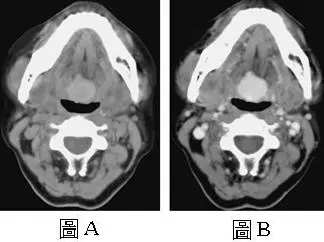

30 歲女性患者,主訴咽喉有腫脹( fullness )的感覺,接受電腦斷層檢查,圖 A為未注射顯影劑的影像,圖 B則為注射顯影劑後的影像,下列何者是最可能的診斷?

舌根部腫塊(tongue base mass)的電腦斷層(computed tomography, CT)影像診斷,重點在於辨識舌甲狀腺(lingual thyroid)的特徵性 CT 影像表現——非顯影劑影像(圖 A)呈現高密度(hyperdense)病灶,注射顯影劑後(圖 B)均勻明顯強化(avid homogeneous enhancement)。

本題呈現兩張 CT 橫切面影像,均為口咽/舌根層面:

圖 A(non-contrast CT,未注射顯影劑):

- 在舌根(base of tongue)中線位置,可見一個**高密度(hyperdense)**的軟組織腫塊,其 CT 密度值(Hounsfield units, HU)明顯高於周圍舌肌組織。

- 腫塊形態規則,邊界清楚,位於中線,呈圓形至卵圓形。

- 在頸部正常甲狀腺位置(甲狀軟骨兩側)未見正常甲狀腺組織——此為重要的陰性發現。

- 非顯影劑下自發性高密度是甲狀腺組織的特徵,因甲狀腺內含有大量碘(iodine),使其 CT 密度值原本即高於軟組織(正常甲狀腺 HU 約 80–120 HU,遠高於肌肉的 40–60 HU)。

圖 B(contrast-enhanced CT,注射顯影劑後):

- 同一部位的腫塊顯示**均勻且明顯強化(avid hom